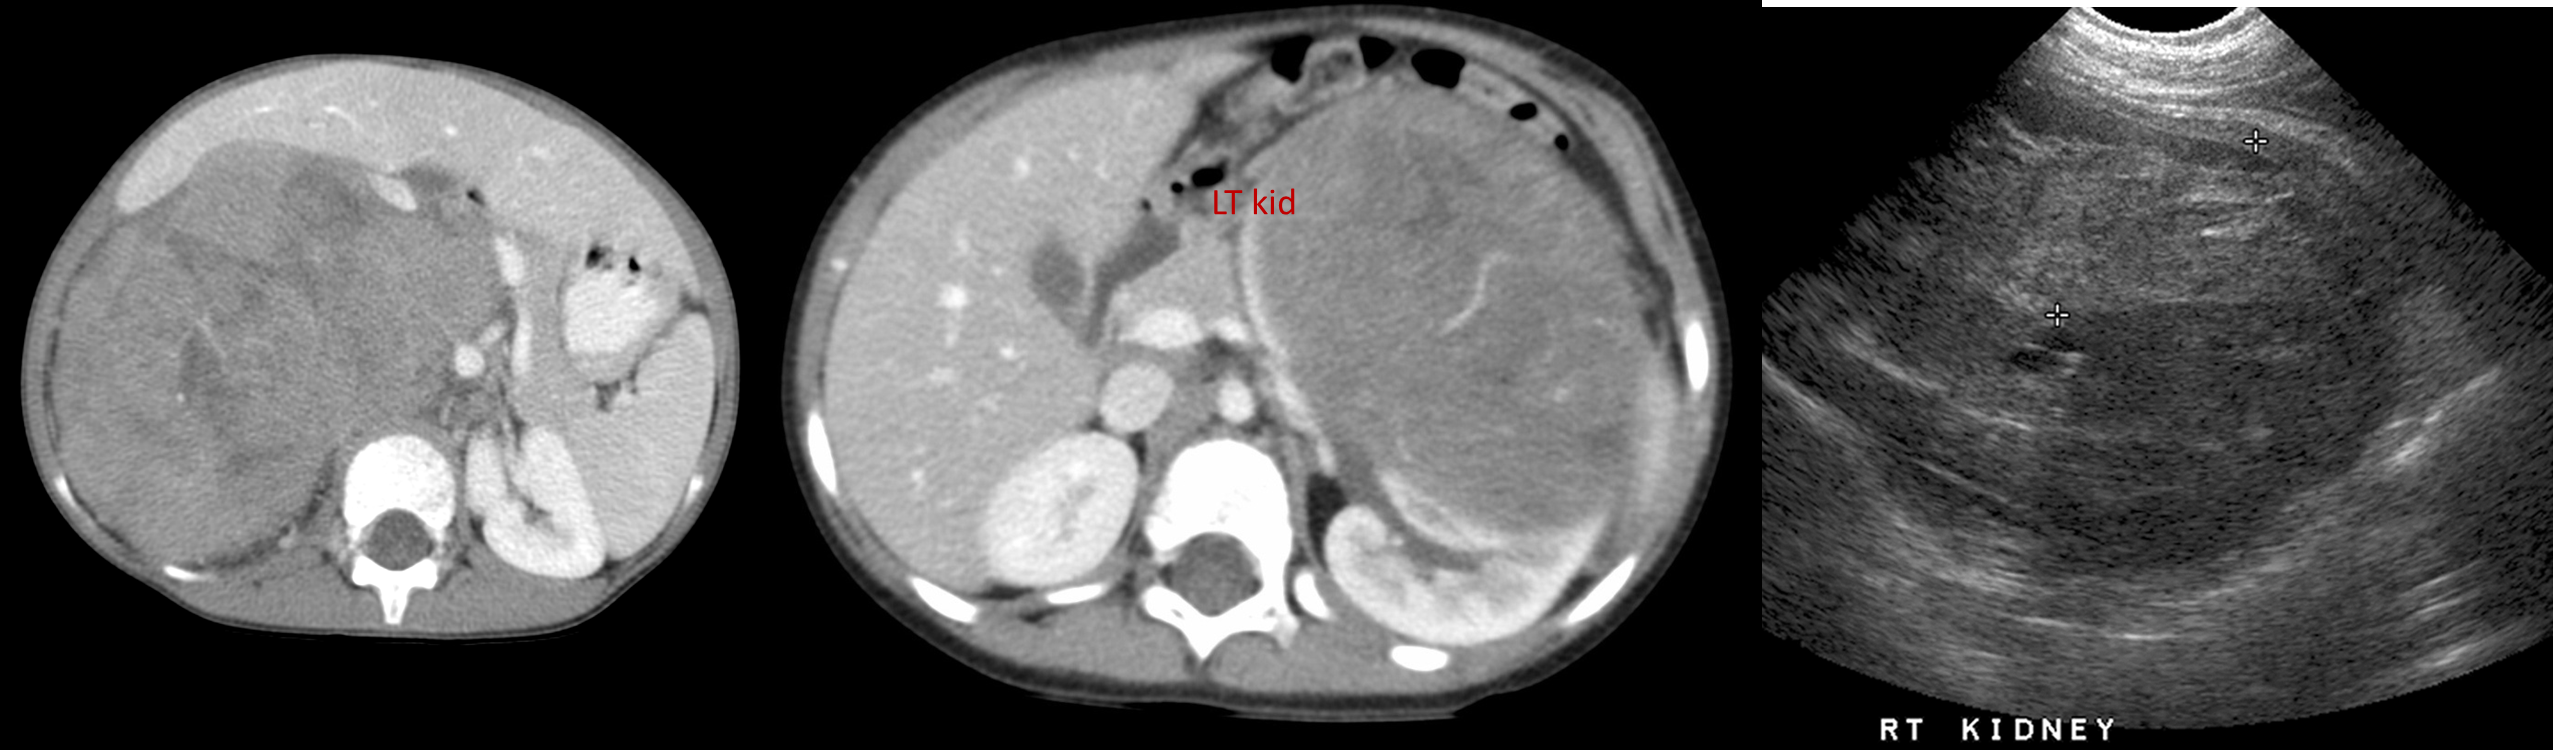

CT : Wilms tumors are heterogeneous soft-tissue density masses with infrequent areas of calcification (~15%) . Enhancement is patchy